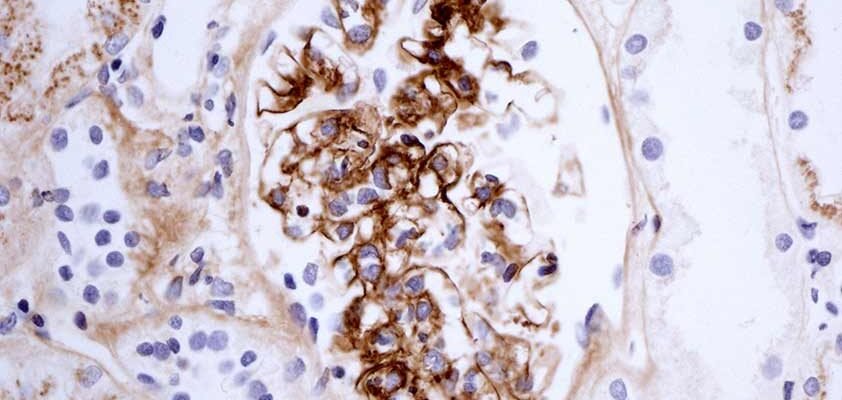

- Біопсія нирок: Так, і ця маленька процедура має велике значення.

Кожен чув про хворобу, але не всі розуміють, що насправді відбувається всередині організму. Хвороба Берже – це розлад, при якому антитіла IgA (імуно-глобулін А) накопичуються в нирках, викликаючи запалення. Ой, думаєте це щось просте? Зовсім ні. Це процес, через який організму важко функціонувати.